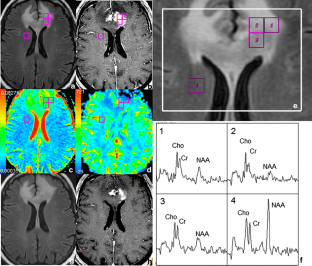

Fig. 1